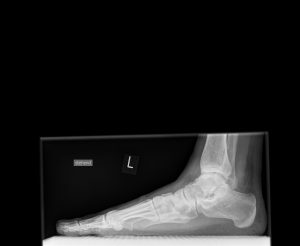

Ein weit verbreitetes Beschwerdebild ist der Plattfuß. Wie sieht dieser genau aus und wie kann er behandelt werden – diesen Fragen stellt sich Dr. Bernd Mayer, Orthopäde und Experte auf dem Gebiet der Fußchirurgie.